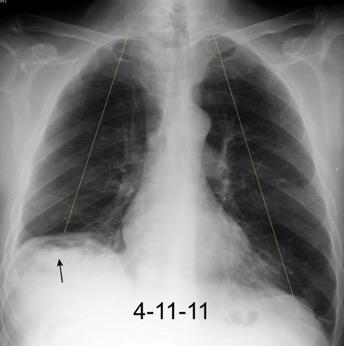

Tromboembolismo pulmonar Diafragma elevado 20%

Consolidación por Infarto pulmonar. (TEP)

Borramiento del hemidiafragma derecho

“Visible en toda su longitud en lateral”.